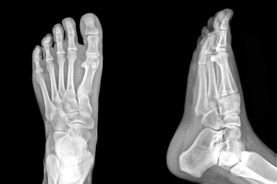

When the only solution to a foot problem is surgery, finding the most qualified and cost effective solution is important. The Red Deer Foot Institute is a group of dedicated Podiatric Physicians specializing in the Medical and Surgical treatment of the Foot and Ankle. Our mandate is to provide the best possible medical, surgical and preventative treatment available. We have been doing this now for over 15 years.

At the Red Deer Foot Institute, our Doctors are trained to specifically treat problems associated with your feet or ankles. Below are several of the most common problems that we see on a day to day basis: